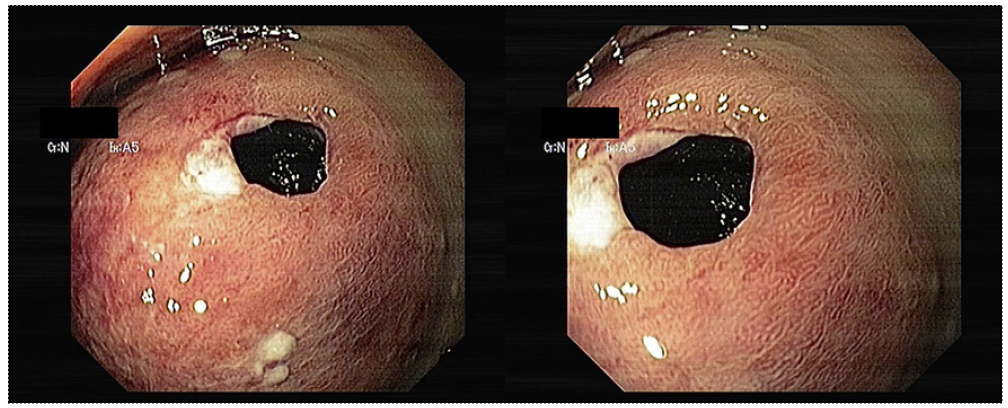

In the setting of an acute lower gastrointestinal bleeding, an urgent colonoscopy after bowel preparation was conducted. Proctologic examination was normal. On digital rectal examination, a soft bulge was felt on the distal rectum, with bright blood being detected. On colonoscopy, a voluminous bulge (approximately 60 × 55 mm) with a congestive appearance was seen in the distal rectum, with a 10-mm orifice being evident on its surface (Fig. 1). Inside this orifice, there was abundant coagulated hematic content, which could not be aspirated. This bulge was passable by the conventional colonoscope, without resistance. There were no other relevant endoscopic findings throughout the colon.

Fig. 1 Endoscopic images showing a voluminous bulge (approximately 60 × 55 mm) with a congestive appearance seen in the distal rectum, with a 10-mm orifice being evident on its surface, compatible with a rectal hematoma.